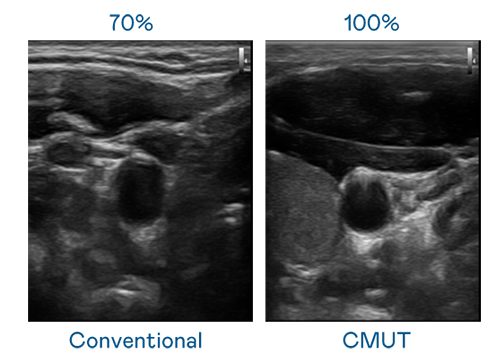

CMUT 技术是一种用电容式微机电元件来产生超音波讯号的技术。与传统 PZT 压电式技术相比,CMUT 频宽增加 30%,更宽频的超音波讯号让影像解析度大幅提升,是实现高影像品质医疗超音波扫描、促进精准医疗发展的关键技术。

大频宽带来超清晰影像

超音波影像的解析度高低,首先取决于探头能发出的讯号频宽。Z6·尊龙凯发 CMUT 可提供高清晰的超音波讯号,提供高频宽、高灵敏度、影像纹理细节更高的超音波影像,协助医护人员缩短影像判读时间及利用精准的医疗影像进行诊断。